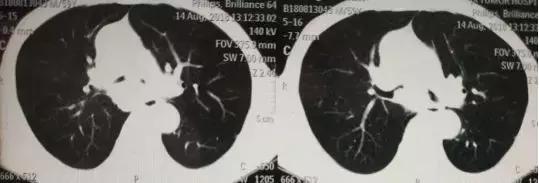

59岁的张先生是个名副其实的“老烟民”,平均一天两包烟抽了将近四十年。直到两个月前,一向身体健康的他突然开始咳嗽,偶尔会咳出*血丝红**,服用止咳药后不好反而出现了气促症状。老张这才意识到情况不妙,到所在省份的肿瘤医院,进行胸片及胸部CT检查后发现气管内长了东西,堵塞了部分气管,左右主支气管也被压迫,导致他呼吸困难。

经人介绍,老张辗转到医院肿瘤科,王专家看过老张的胸部CT后认为大概率是肺癌,但问题是肿瘤长在气管下段,左右主支气管也显著狭窄,随时有窒息的可能。所以,要先保证患者能够活下来,才有可能接受后续的治疗。